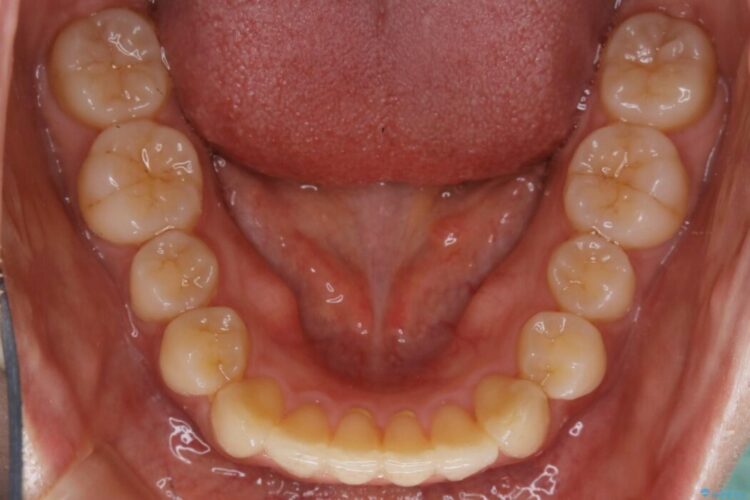

下の前歯のガタつきが気になるとご来院された患者様です。

インビザラインのライトパッケージにて、歯列拡大とディスキング(IPR)をを行いスペースをつくり非抜歯で治療を行いました。

ディスキング(IPR)

歯のガタつきをとるためのスペース作りの方法の一つにディスキング(IPR)という方法があります。

歯と歯の間を一ケ所あたり最大0.5mmまでの範囲内で削ることで歯自体が少し小さくなり、それにより作られるスペースを数ヶ所分合わせることで合計で数mmの大きなスペースが作れるという方法です。

当院ではなるべく歯の機能や見た目に影響の出ないよう、作業時に拡大鏡の使用や削るタイミングの微調整を行っています。